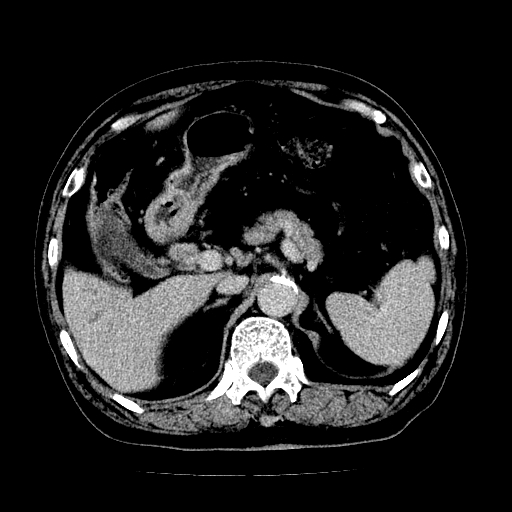

男,71岁,皮肤黄染四天。

肝内外胆管及胆总管上段扩张,考虑为梗阻所致,建议mrcp检查。

考虑胆总管癌并肝内外胆管扩张。

胰腺上端胆总管内见软组织影,强化不明显,结合临床,还是考虑低位梗阻性黄疸,胆总管癌可能性大